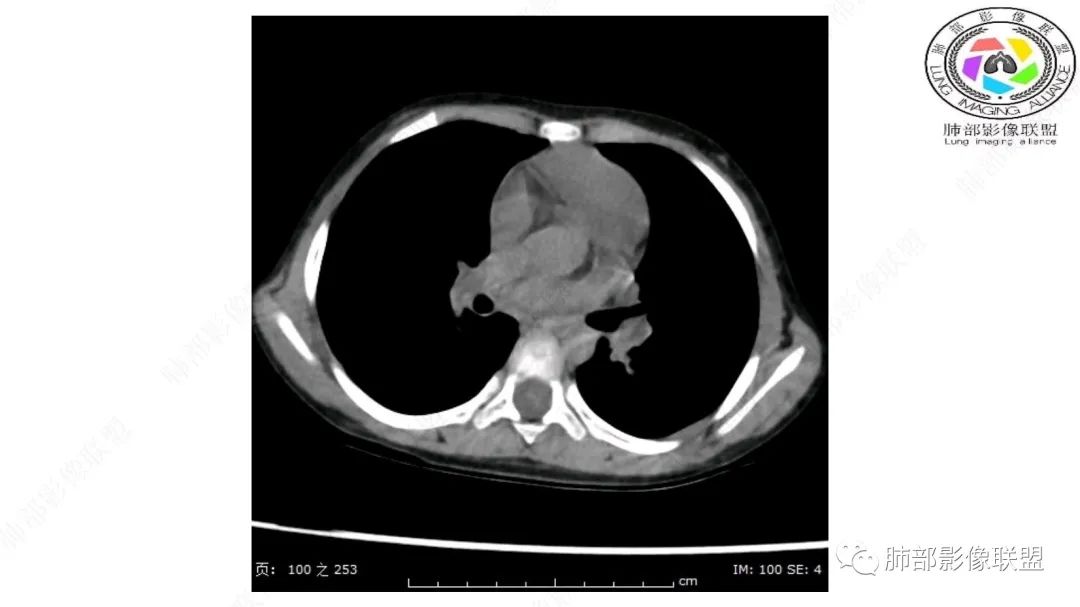

三岁小儿,右侧纵隔巨大脂肪密度肿块,肺动脉穿行其中,密度欠均匀,未见明确实性成分,纵隔脂肪母细胞瘤,冬眠瘤鉴别纵隔脂肪增多症(多弥漫对称)。

跨肺门,包绕肺血管分支,邻近肺组织受压肺不张。

前方突入胸壁

有高密度影,有其他的血管来源。

病灶属于交界区,主体位于肺内,占位效应明显,前方突入胸壁,胸腺受压变形,胸膜显示欠清楚;病灶包绕上叶肺动脉;似乎有体动脉供血。符合肺内的点:包绕上叶肺动脉分支;符合纵隔的点:前方似乎突入胸壁,与胸腺关系比较密切,但是与上腔静脉的关系提示病灶不支持纵隔来源,前纵隔的常规会将上腔静脉受压后移、外移,这是不符合的。

从这个角度符合肺内的,有一点不太踏实的是:似乎突入前胸壁。

第二个问题:定性:脂肪为主病灶明确:脂肪瘤?脂肪肉瘤?畸胎瘤?

内部血管明显,部分病灶密度增高,单纯脂肪瘤不支持。可惜的是:没有提供CT值:是否强化?如果强化,警惕恶性;胸腺肯定不符合,胸腺会将上腔静脉朝后推移。

1.右上肺-纵隔交界区巨块影,主体位于右肺一侧,紧贴胸腺、头臂干、右锁骨下动脉、上腔静脉、奇静脉等,不能分离,但病灶整体边界清楚。注意上述相邻腔静脉等结构未见受压变形,纵隔亦未见明显向左推移,至少提示两点:

1)病灶相当柔软。

2)位于纵隔内或纵隔胸膜的可能性较小,因为受纵隔胸膜反作用力影响不明显。

2.肺动脉穿行也许是肺内来源最重要支持点!

CT扫描对脂肪类肿瘤常有独到价值。肿块孤立、边界清楚,未见周围浸润,较均匀脂肪样低密度,高度提示为良性!

发生于成人为脂肪瘤表现,婴幼儿自然会想到脂肪母细胞瘤。两者生物学行为并无本质区别。